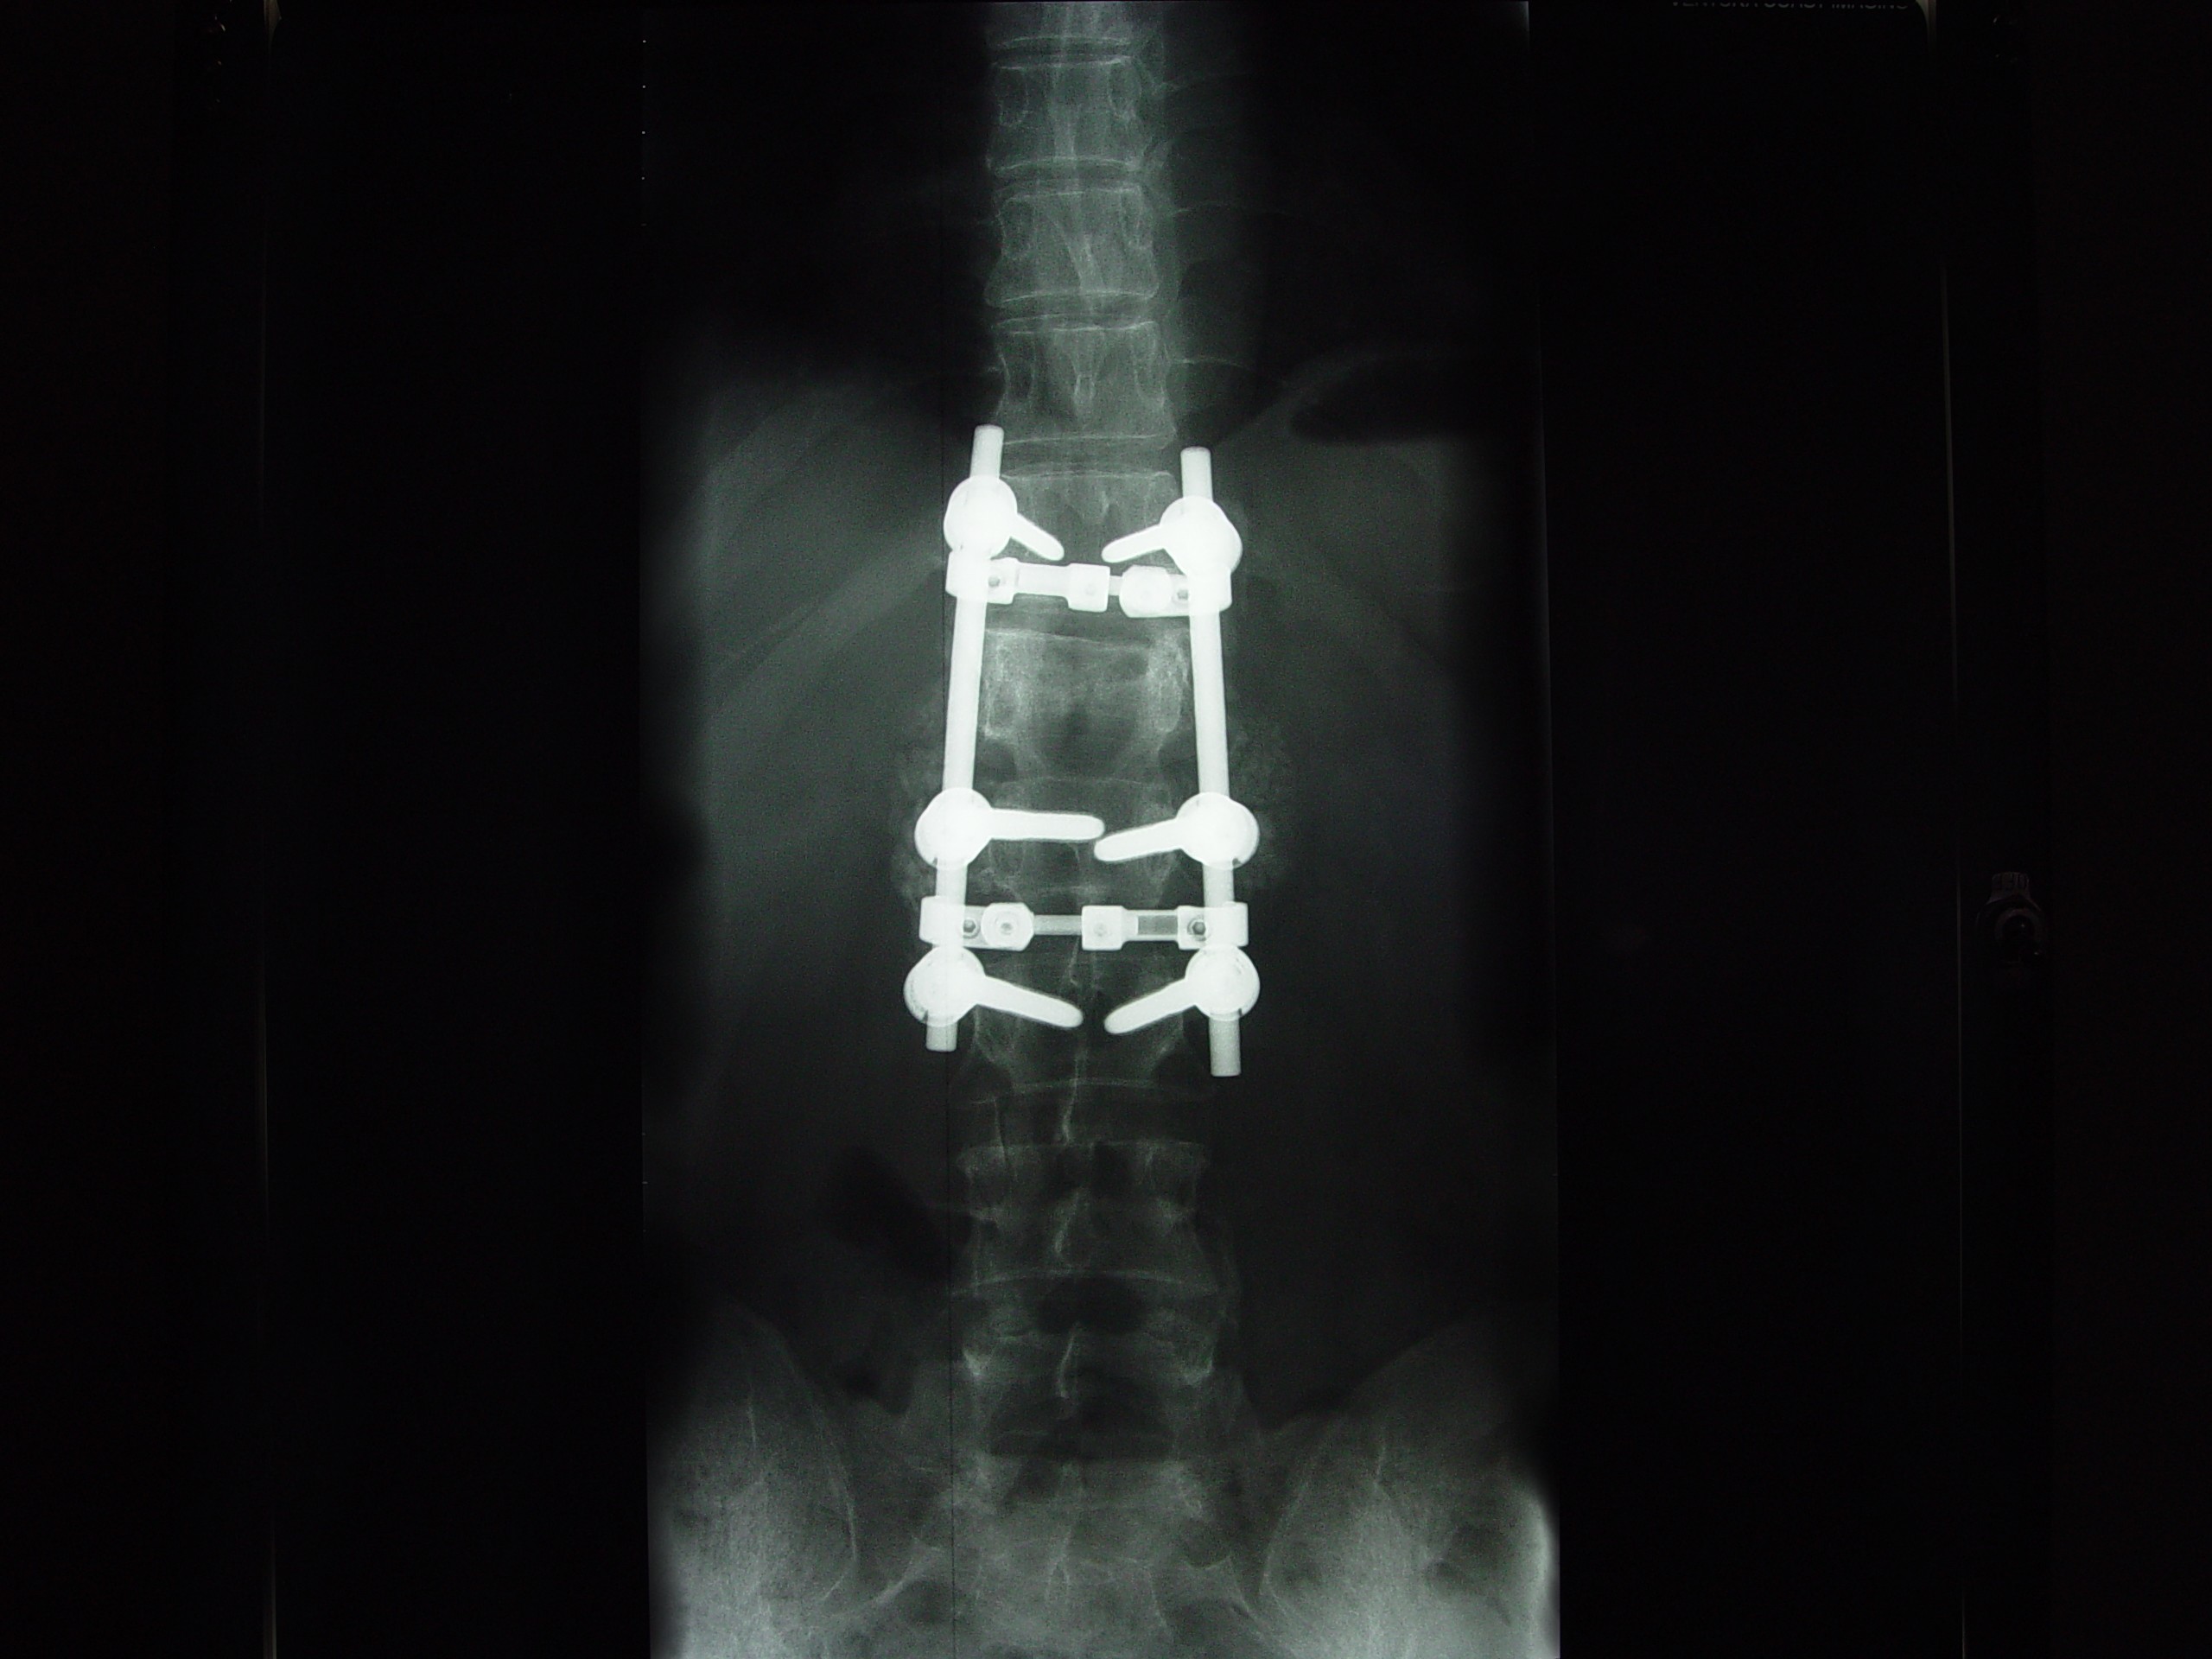

Mini is at VCMC in the I C U.. He has a Badly shattered and Broken L1 vert in his back from impact during a stalled landing approach into a field...

Doctors will be operating More than likely on Sunday the 16th to stabalize his injury... through his CHEST !~! He has Pieces TOUCHING his spinal cord that could paralize him if he moves wrong etc... He is Taped to a BACK BOARD tonight and will be untill SURGERY is COMPLETED and the injury is Stabalized etc...